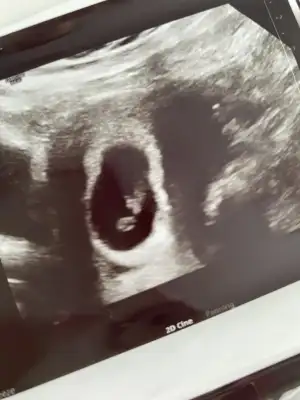

Birde şöyle var tek olan diğer foto bide ikisini attım

Eklentiler

• 7C2B197E-B980-41A2-923F-AB85E3E7A1A9.webp

7C2B197E-B980-41A2-923F-AB85E3E7A1A9.webp

25,6 KB · Görüntüleme: 76

• 3AAD7856-5AE0-4593-97C1-B43AD244C929.webp

3AAD7856-5AE0-4593-97C1-B43AD244C929.webp

33,6 KB · Görüntüleme: 83